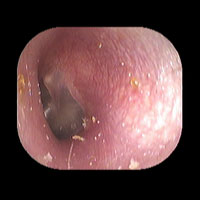

左急性中耳炎(重症)

鼓膜がやや赤くなって腫れています。鼓膜の奥に膿が透けて見えています。抗生剤の内服で鼓膜切開を行わずに22日目で治りました。

22日目